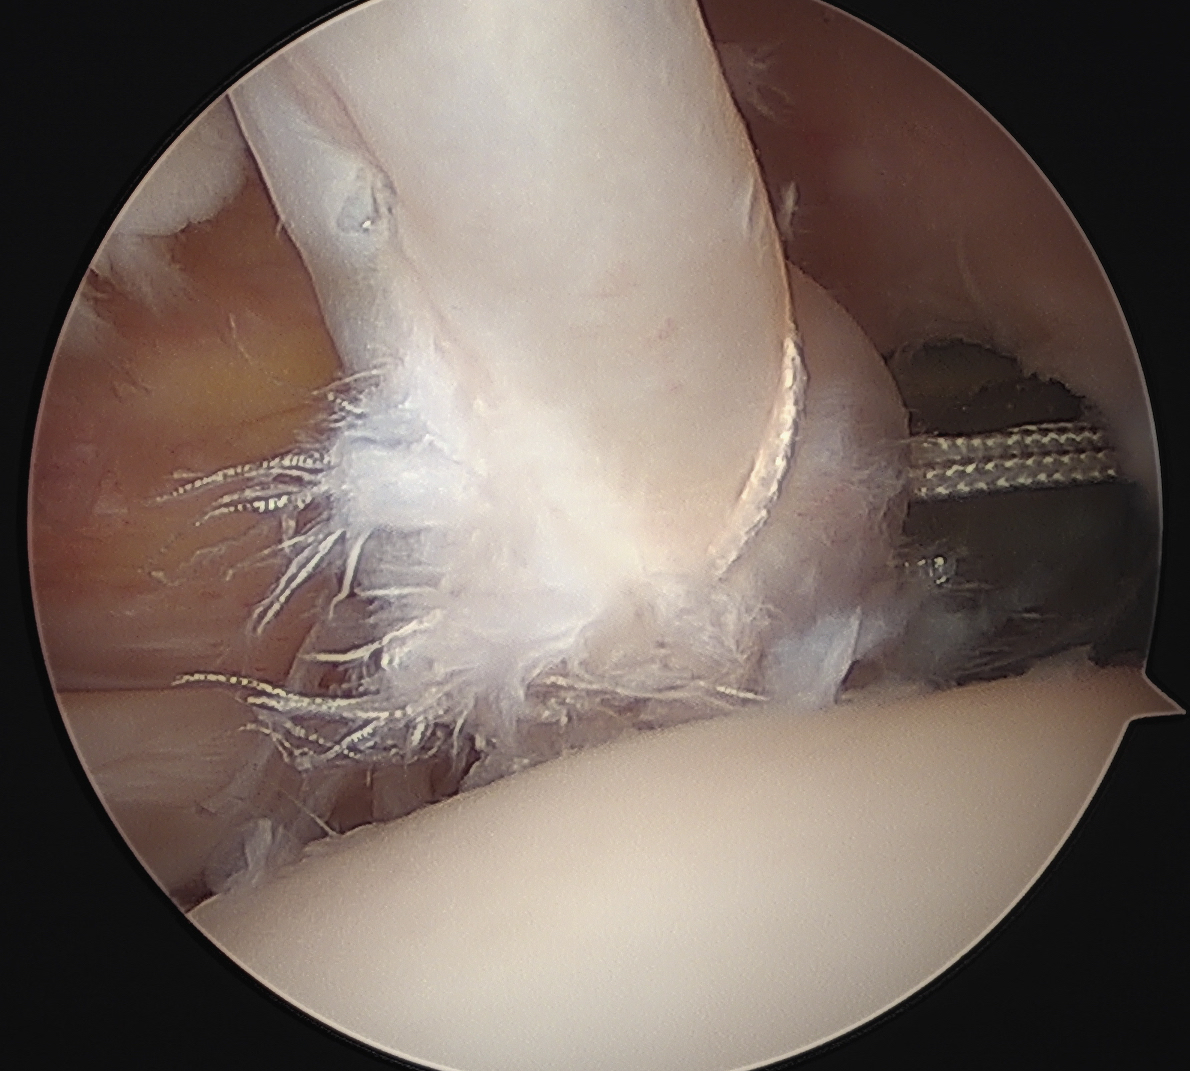

Anterolateral portal of Wilminton at anterolateral border of the acromion used to tag and release biceps

Insert anchor through anterior portal into subscapularis footprint

Suture passage through anterior portal or anterolateral portal and tie sutures through anterior portal

Lateral traction sutures placed in subscapularis, then cautery used to remove scar tissue and recreate rotator interval